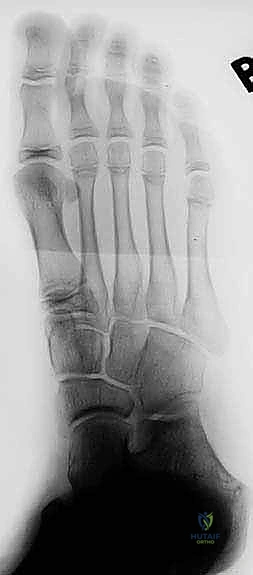

- الأشعة السينية التقليدية (X-Rays): يتم أخذ صور بوضعيات خاصة (مثل وضعية Harris-Beath) لرؤية المفصل تحت الكاحل. قد تظهر الأشعة السينية الائتلاف العظمي بوضوح، بالإضافة إلى علامات ثانوية مثل "علامة حرف C" (C-sign) التي تدل على تشوه في عظم الكاحل، أو وجود نتوءات عظمية (Osteophytes) تشير إلى بداية خشونة المفاصل المجاورة.

- التصوير المقطعي المحوسب (CT Scan): يُعد المعيار الذهبي (Gold Standard) لتشخيص ائتلاف الكاحل العقبي. يطلب الدكتور هطيف إجراء أشعة مقطعية ثلاثية الأبعاد، حيث توفر صوراً متناهية الدقة للتركيب العظمي، تحدد حجم الائتلاف، موقعه الدقيق، ونسبة إصابة المفصل. هذه الخطوة حاسمة جداً قبل اتخاذ قرار الجراحة.

- التصوير بالرنين المغناطيسي (MRI): يتم اللجوء إليه إذا كان الائتلاف غضروفياً أو ليفياً ولم يظهر بوضوح في الأشعة المقطعية، كما يفيد في تقييم حالة الأوتار والأربطة المحيطة، وتحديد مدى التورم في نخاع العظم (Bone Marrow Edema) الناجم عن الإجهاد الميكانيكي.